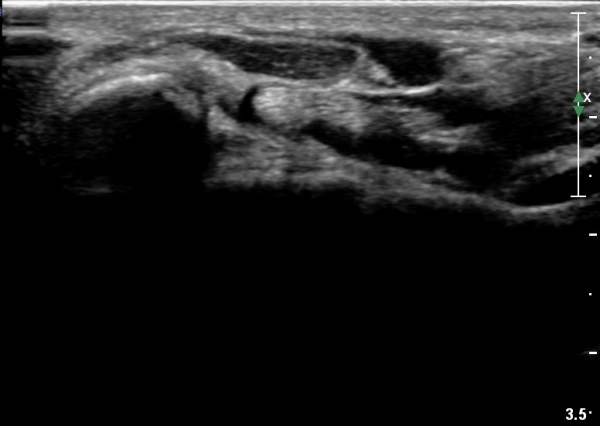

¼ö±Ù°ü ±ÙÀ§ºÎ Ⱦ´Ü¸é°Ë»ç¿¡¼­ Á¤Á߽ŰæÀÇ ºÎÁ¾ µî ƯÀÌ ¼Ò°ßÀÌ º¸ÀÌÁö ¾Ê´Â´Ù(»çÁø 2).